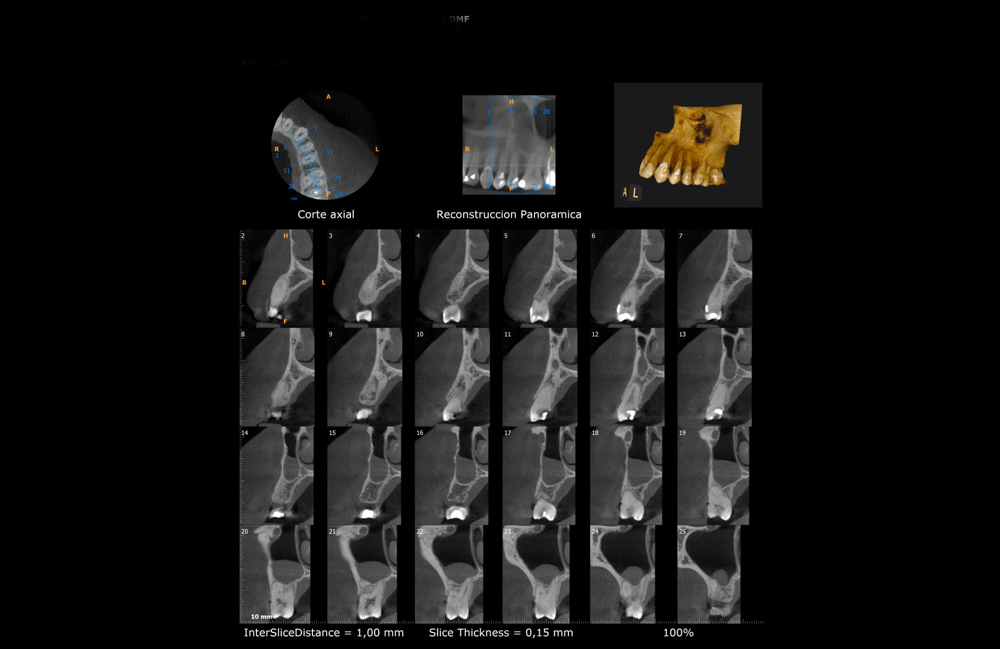

- Se pueden visualizar imágenes de alta calidad en los tres planos del espacio.

- Reconstrucciones tridimensionales a escala real de 1:1.

- Cortes tomográficos a diferentes escalas.

Los tomógrafos computarizados Cone Beam pueden ser utilizados en la practica clínica para el diagnostico y el plan de tratamiento en diversas especialidades odontológicas, tales como Cirugía, Implantes, Patología Oral, endodoncia y traumatología.